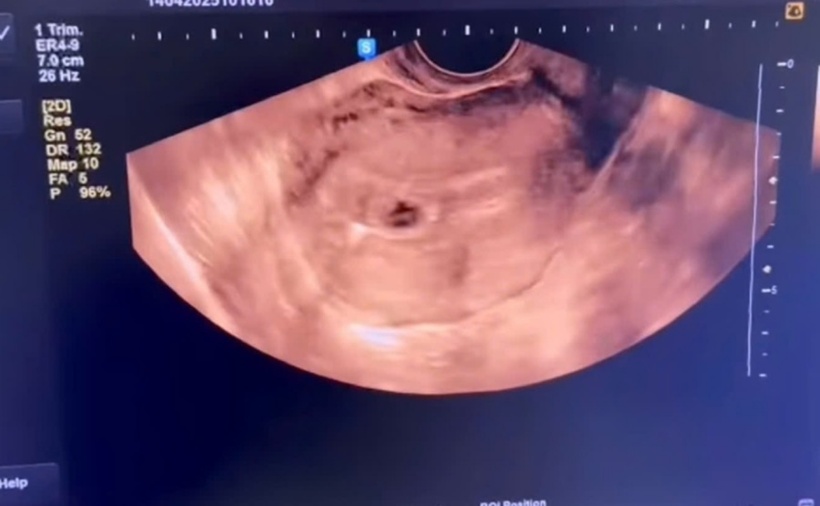

Hình ảnh siêu âm thai của chị B.T.T. Ảnh: Sở Y tế Phú Thọ.

Bốn năm trước, người phụ nữ này đã thực hiện kế hoạch hóa gia đình bằng phương pháp đặt vòng tránh thai. Tại Trung tâm Y tế huyện Thanh Sơn, sau khi thăm khám và siêu âm, kết quả cho thấy tử cung kích thước lớn hơn bình thường, trong buồng tử cung hình ảnh có túi thai, chị được kết luận đang mang thai tuần thứ 4.